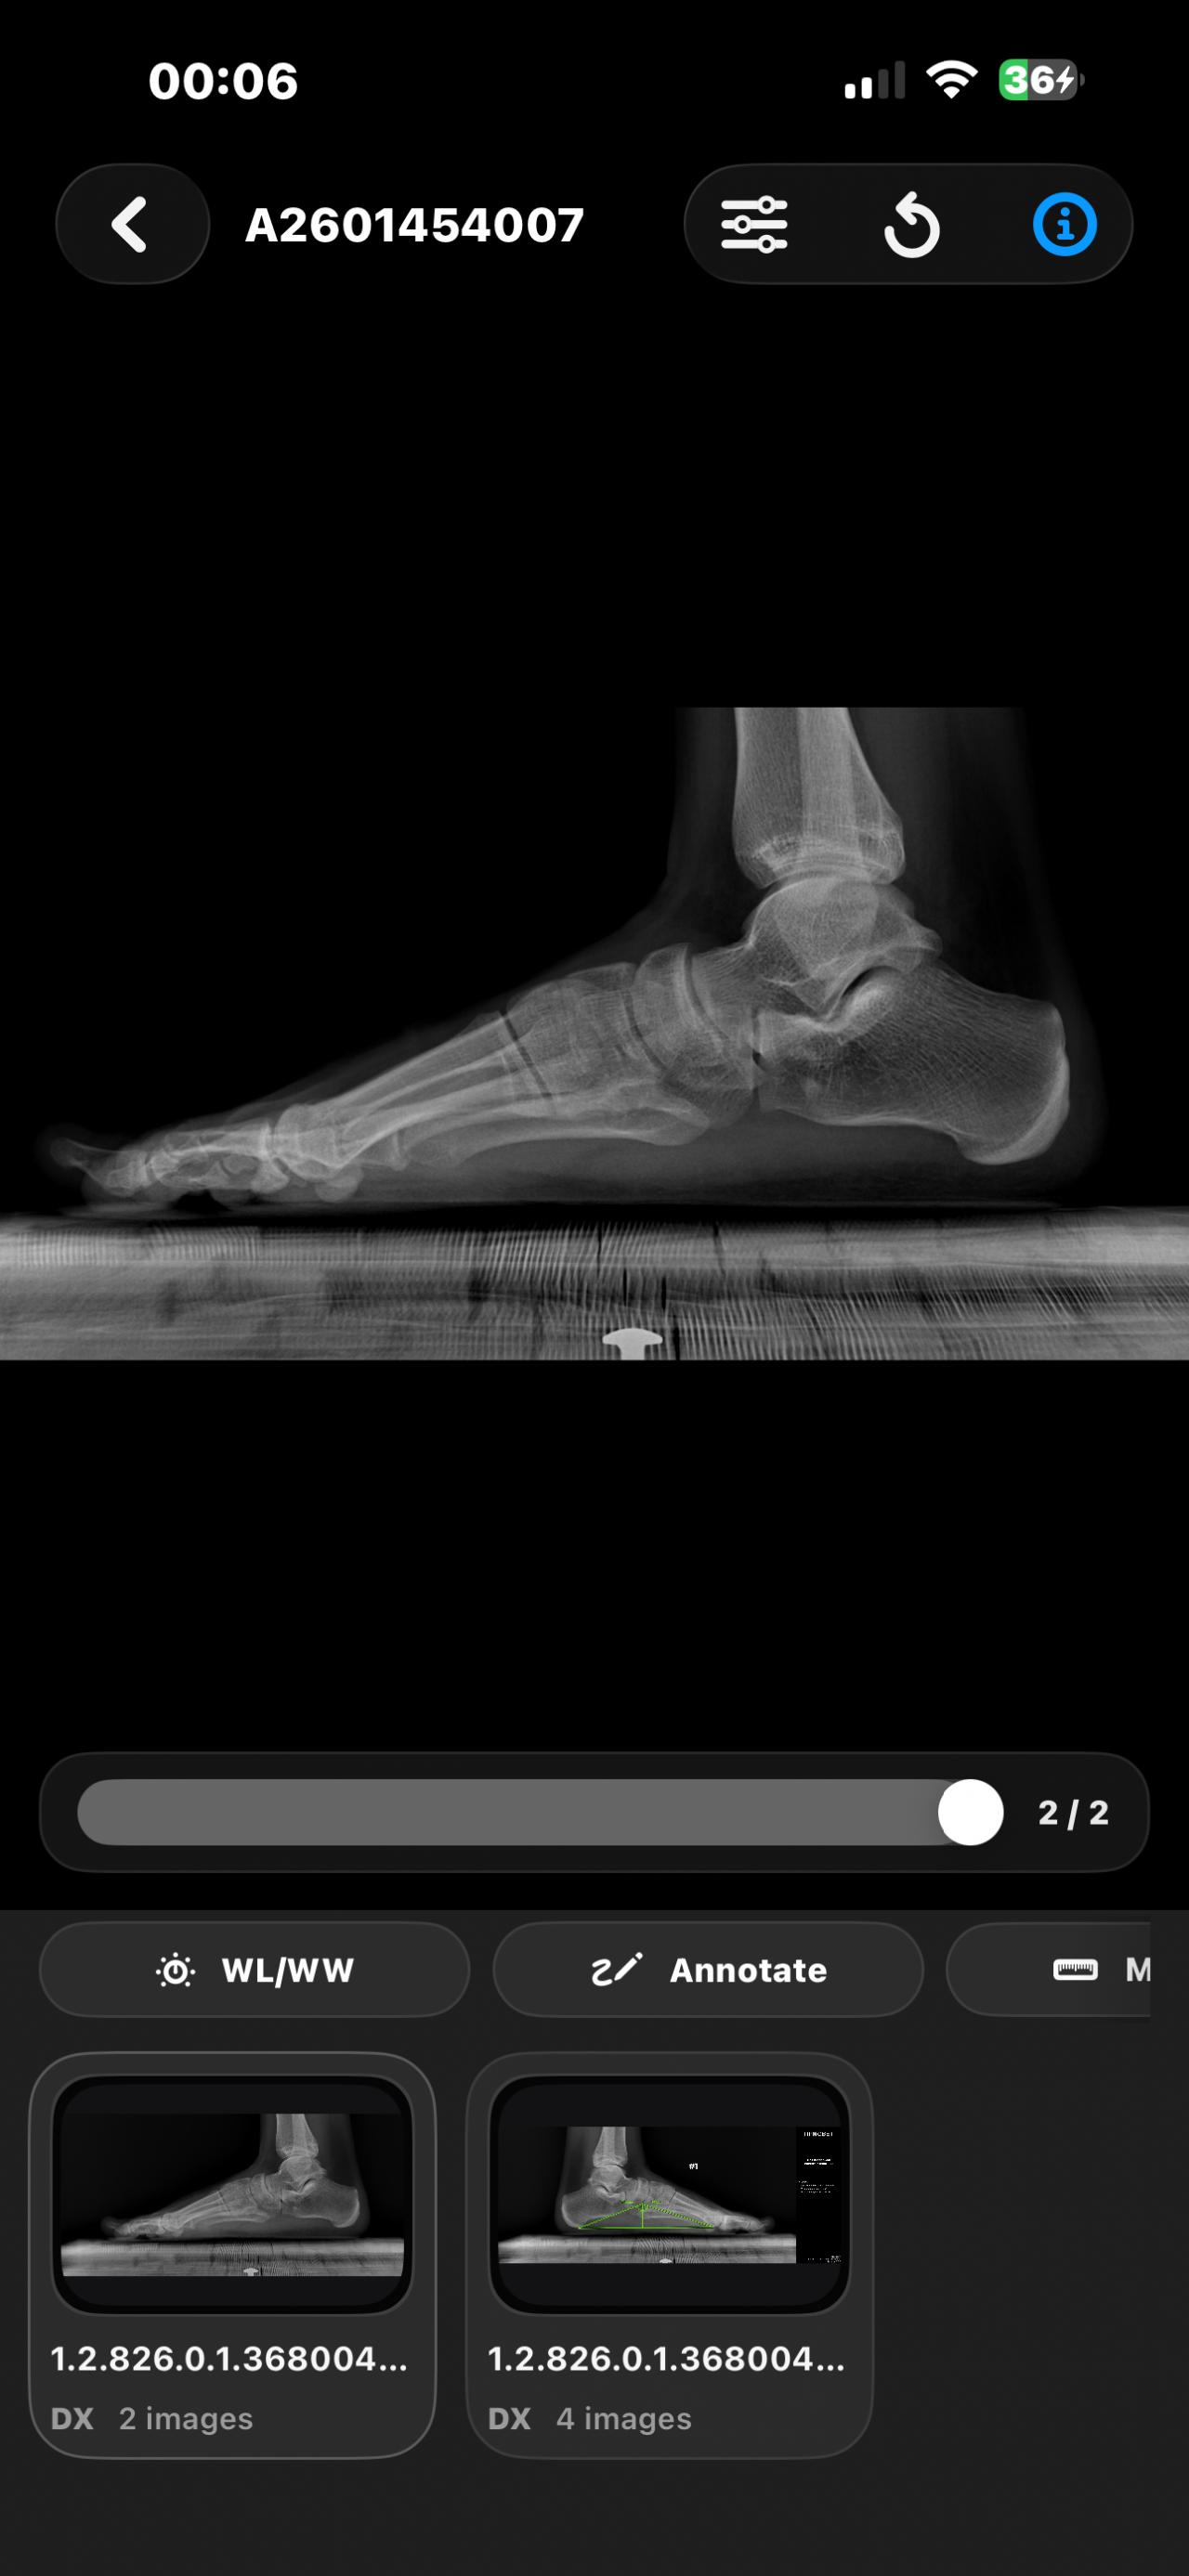

Открыты ли зоны роста. Смогу еще вырасти?

Здравствуйте, мне 16 лет и рост ~173см и мне очень хотелось бы узнать, открыты у меня зоны роста или нет? Сверстники все по 180-185 см и на их фоне я чувствую себя не очень комфортно. Сколько сантиметров я смогу прибавить в росте? Спасибо за ответ!